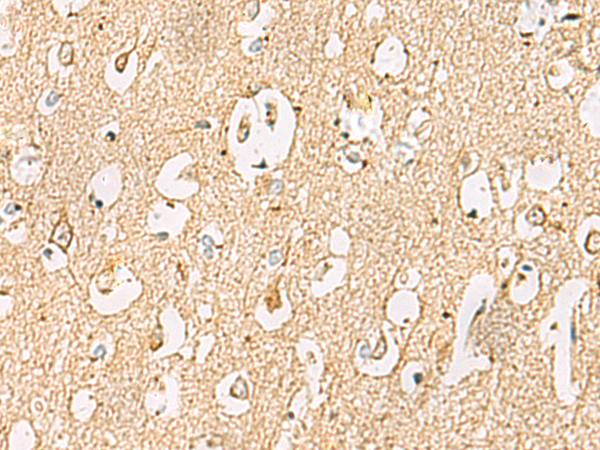

The image is immunohistochemistry of paraffin-embedded Human liver cancer tissue using (LRRC28 Antibody) at dilution 1/60.

The image is immunohistochemistry of paraffin-embedded Human brain tissue using (LRRC28 Antibody) at dilution 1/60.